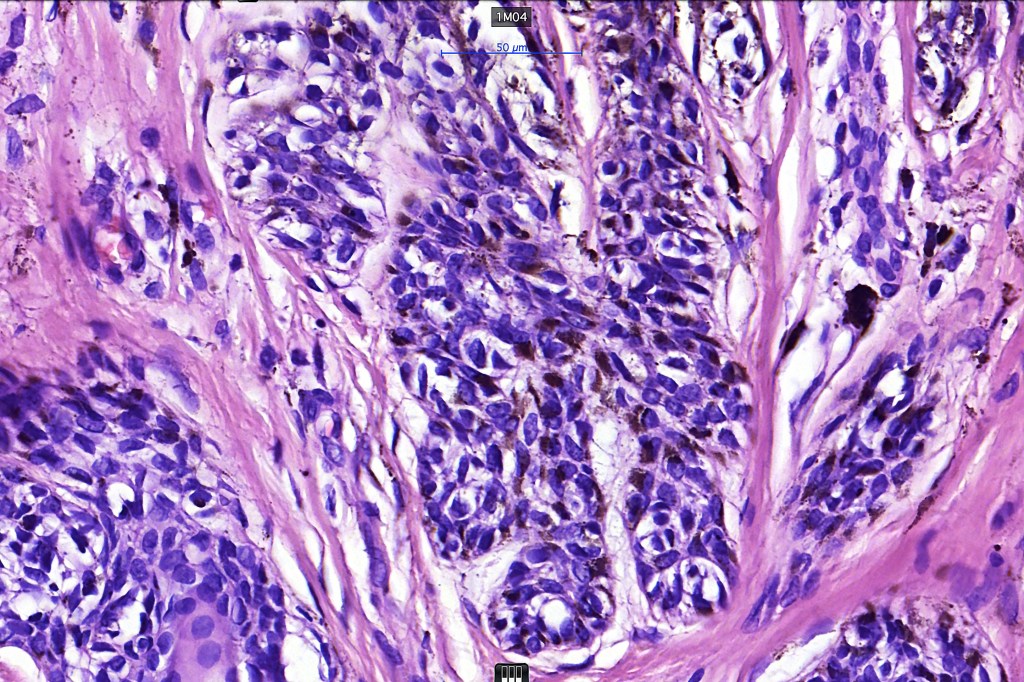

•Cytological atypia- mild, moderate & severe (or more recently, low & high grade (WHO). The problem with the new WHO classification is that mildly dysplastic nevi are now included with the banal nevus category and moderate is low grade and severe is high grade. In all likelyhood, most pathologists will include mild & moderate atypia in the low grade category.

•Variation in the degree of atypia within any one lesion is commonly present

•In compound lesions, the nest size should be smaller than the junctional ones and the degree of atypia the same or less

Dysplastic nevus in the majority of cases is instantly recognizable, often at low power. The most important differential diagnosis is obviously melanoma. In junctional lesions, widespread/uniform high grade atypia, frequent mitoses and Pagetoid spread are indicative of in situ melanoma. In compound lesions, dermal nests larger than junctional ones, expansile dermal nests, severe atypia and mitotic activity indicate the presence of melanoma

Dysplastic nevus with early melanoma